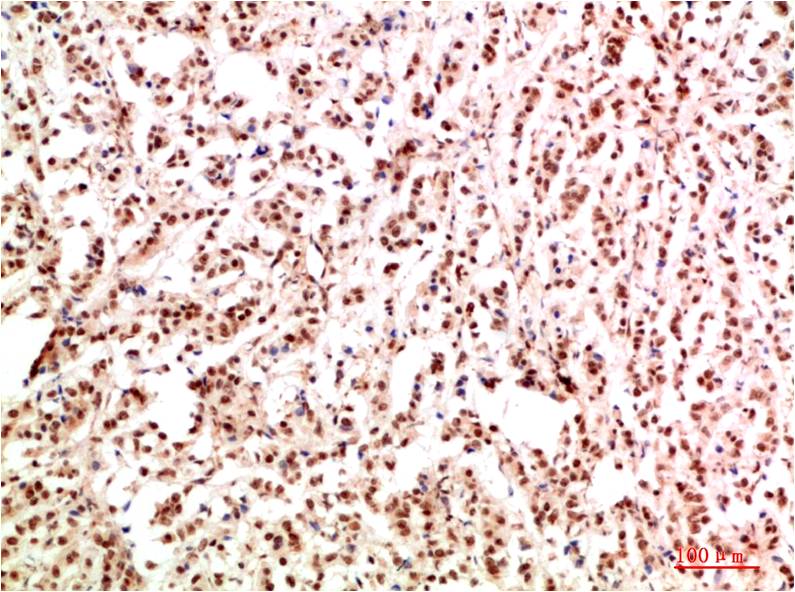

TTR Mouse Monoclonal Antibody(5G9)

Catalog NO.:BE3687

Applications :WB, IHC

Reactivity :H

| Recommended dilutions: | WB 1:1,000-2,000 IHC 1:100-200 |

| Specificity: | The TTR Mouse Monoclonal Antibody can detects endogenous TTR proteins. |